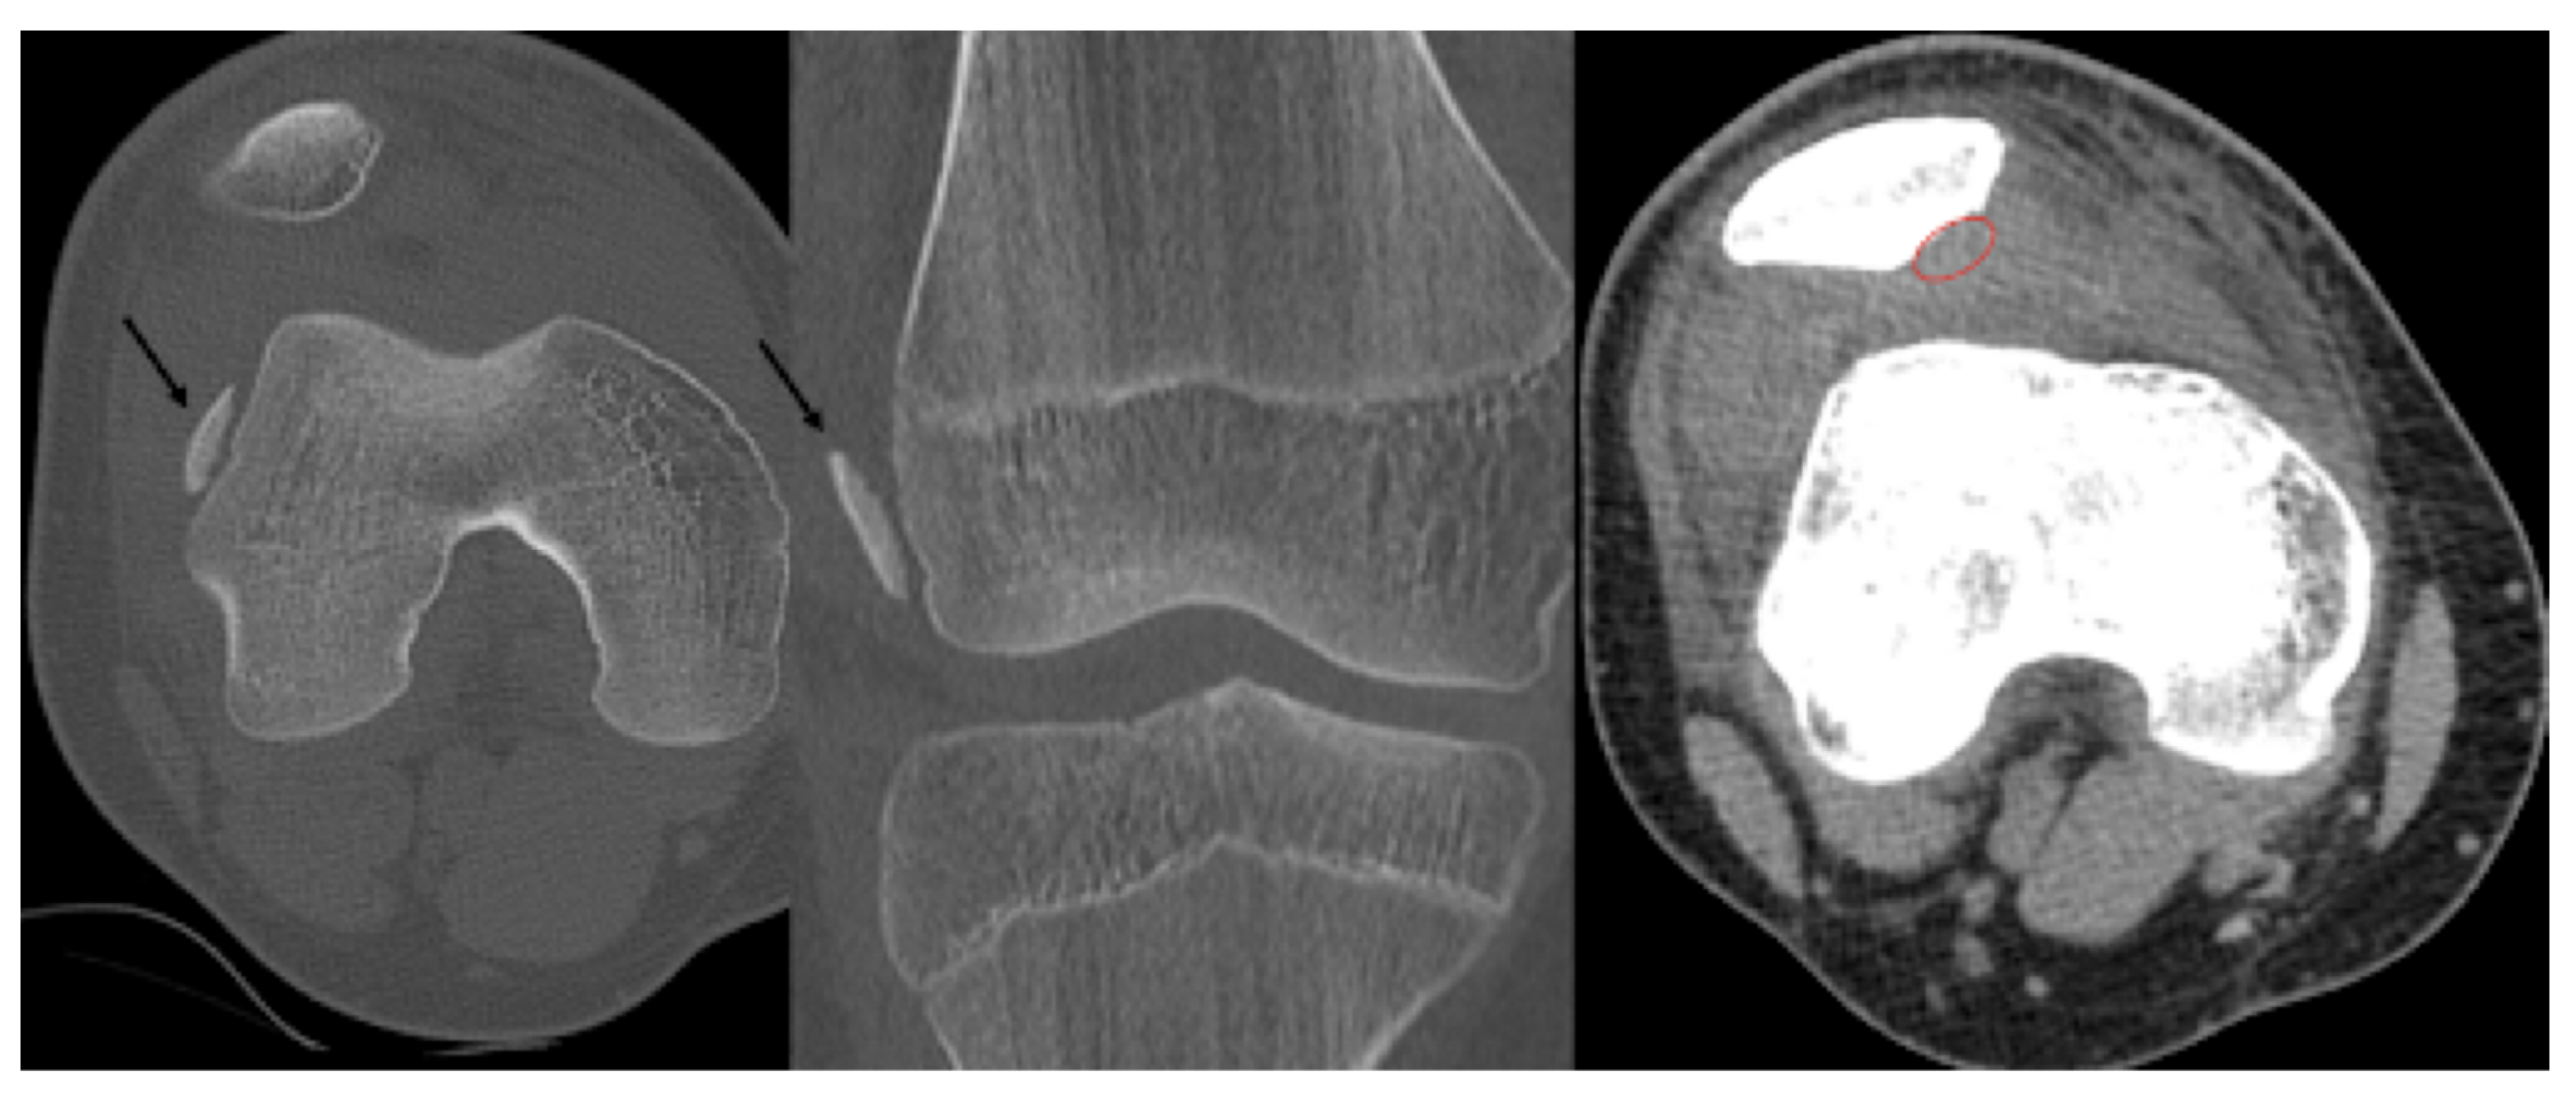

The patient was hospitalised for two days and received physiotherapy one day after surgery in the form of CPM. Weight-bearing was limited at first, with a gradual increase throughout the recovery period until week 4. Four weeks after the operation, the weight-bearing capacity was near 100% and the patient could walk without a limp, with full extension and flexion. A control X-ray was performed in the control examinations on day 10 and weeks 3, 6 and 12 (Figure 6).

Figure 6.

Postoperative X-ray presents the proper position of the osteochondral fragment of the patella (left image) on which the nails (red circle) are difficult to visualise.